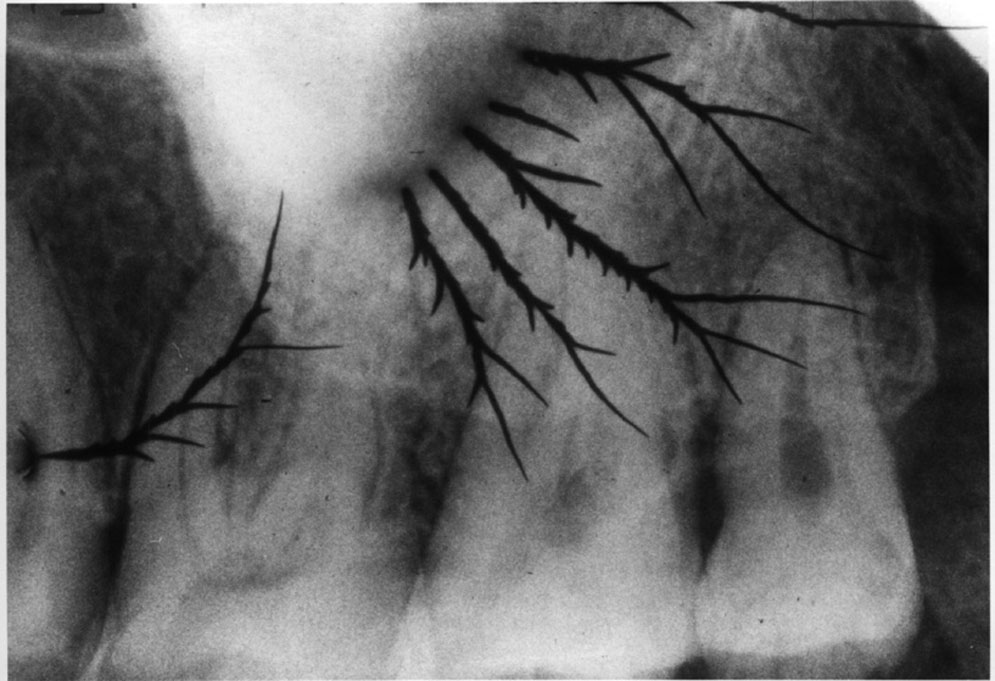

Static Electric Discharge

Damage from static electricity usually occurs as the film is prepared for processing. The synthetic material in some office fabrics can cause a static discharge to jump to the film, particularly when the darkroom humidity is low. Protective latex gloves can cause static electricity that produces a black, smudge-like image. Usually however, the damage is done as the film comes out of the packet and friction between sliding components generates a static charge sufficient to energize the silver bromide emulsion. The resulting artifact appears as radiolucent lines and/or areas, often with a “tree-like” configuration, as in Figure 12. Static electricity can also cause a localized overexposure.

Figure 12. Static electrical discharge.

Figure 12